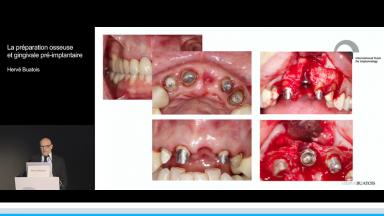

La préparation osseuse et gingivale pré-implantaire

Hervé Buatois

Cette présentation expose les techniques de préparation osseuse et gingivale pré-implantaire dans les cas où les volumes osseux ne permettent pas la pose d’implant dans un axe prothétique optimal.

La pose d’un implant est un acte prothétique pouvant nécessiter une reconstruction afin d’éviter une compensation implantaire et/ou prothétique. La gestion des différents types de défauts osseux est un véritable challenge d’autant plus en secteur esthétique. Il est primordial de déterminer le niveau de difficulté d’une réhabilitation implantaire afin d’établir un pronostic et d’assurer un résultat esthétique à long terme au patient.